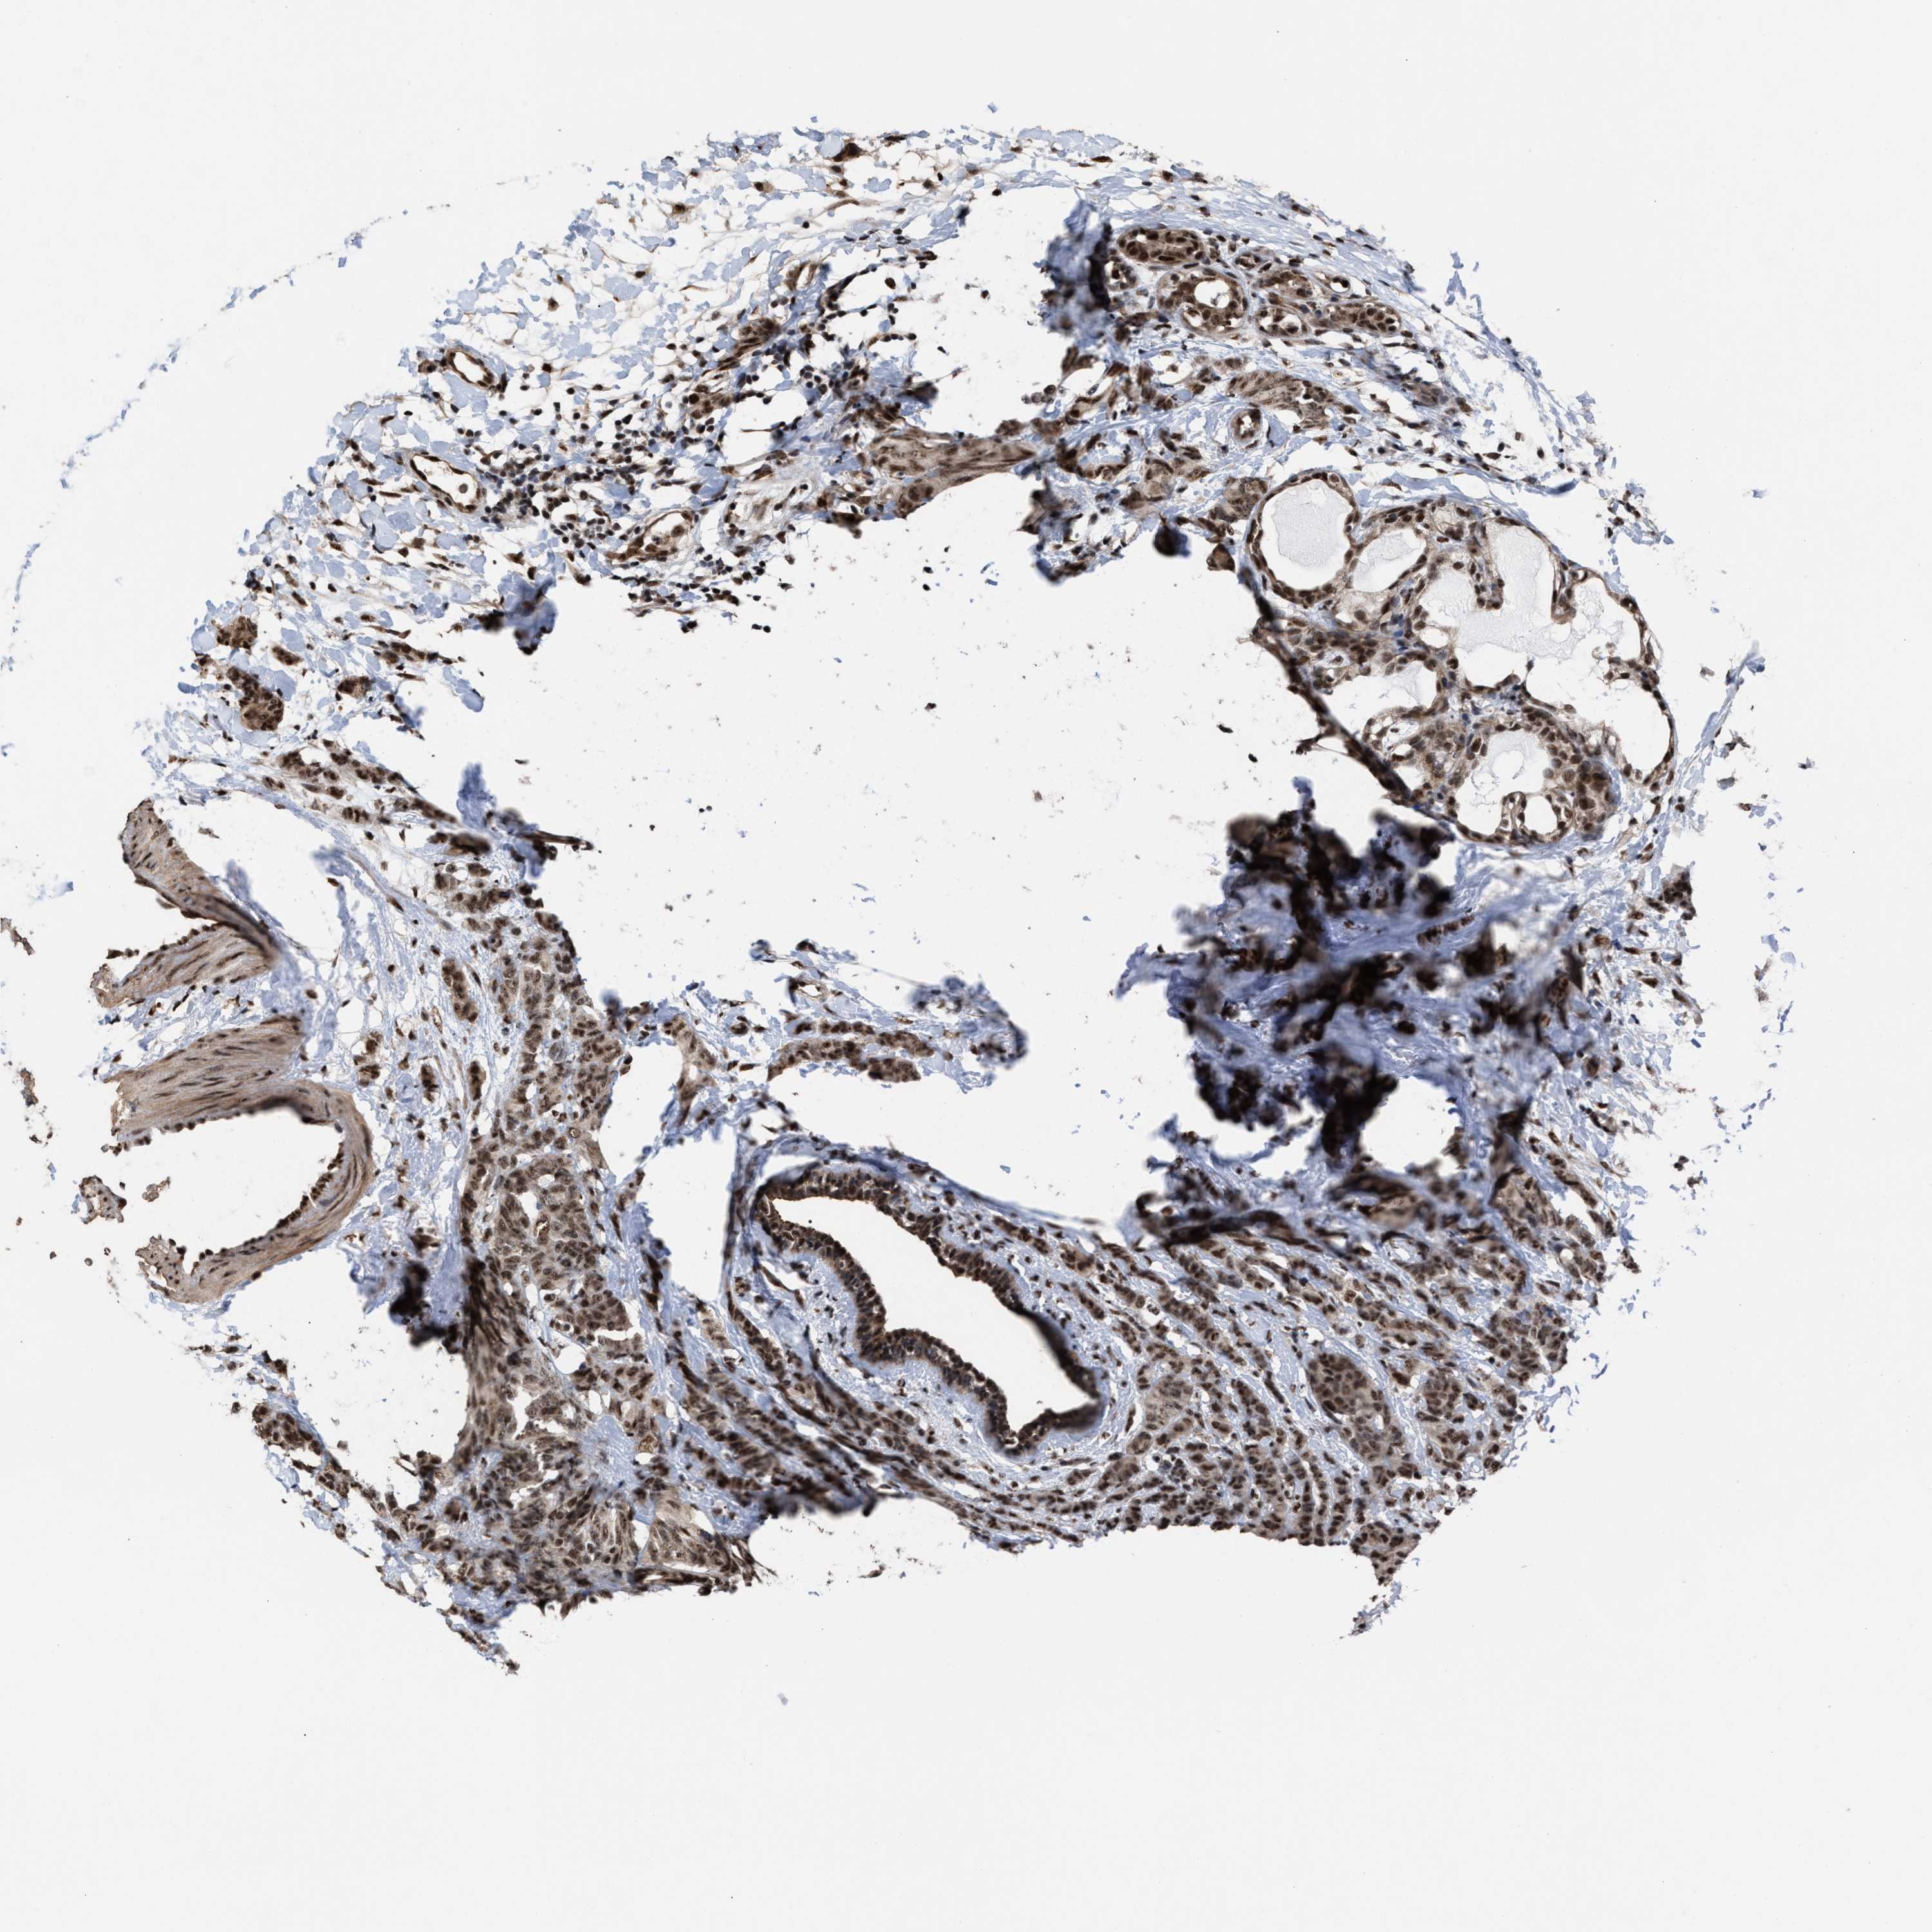

BRCA TCGA BRCA VALIDATION PROTEIN EXPRESSION

ANTIBODIES

AND

VALIDATION